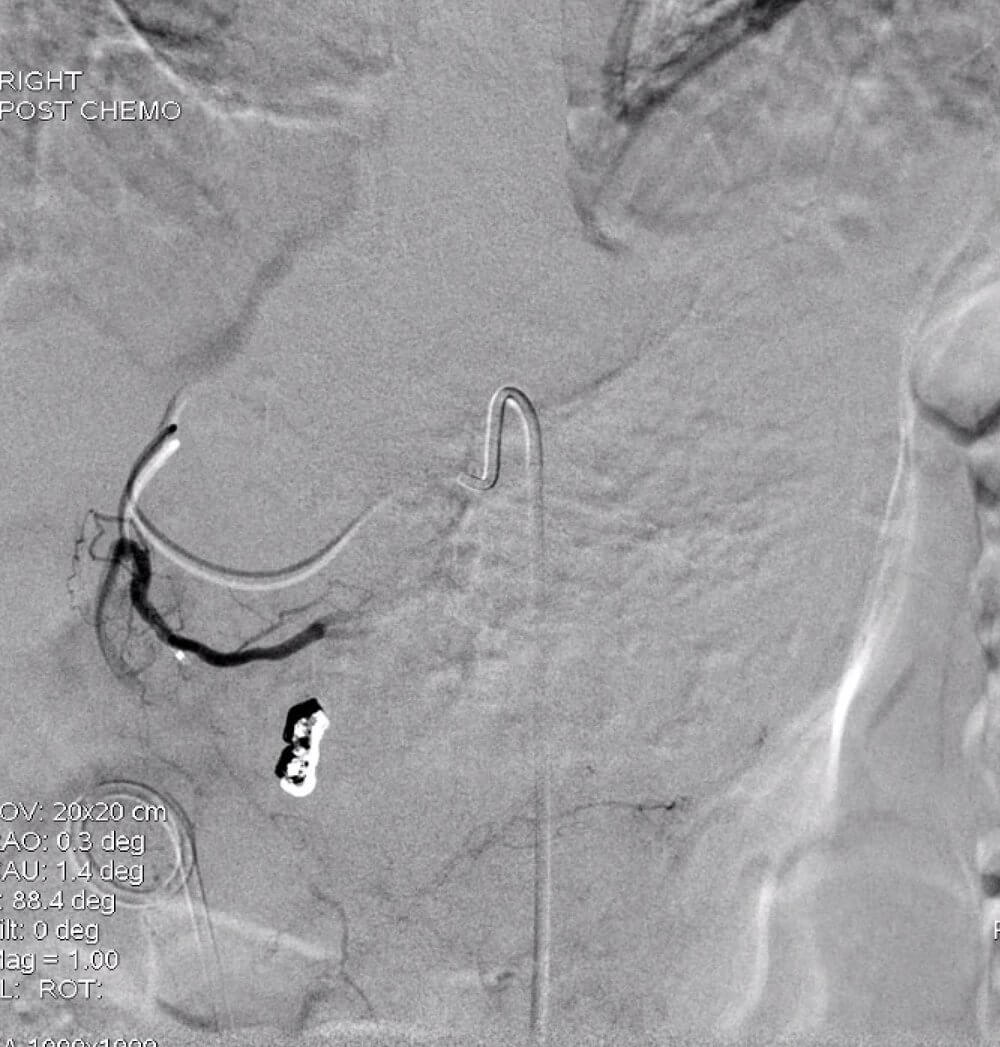

Selective chemoembolization of the left lateral hepatic mass was performed. Chemoembolization via a right common femoral approach was utilized. A Hi-Flo Renegade microcatheter and Fathom microwire were used to select the arterial branches supplying the dominant hypervascular segment 2/3 mass and selective chemoembolization with 100-300 um LC Beads with 75 mg of Doxorubicin was performed.

Post-embolization angiogram demonstrating successful embolization of the branches supplying the tumor.